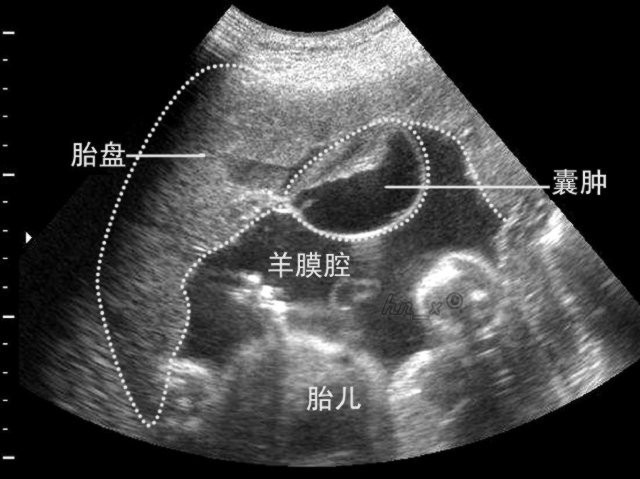

受精卵在著床時(shí)會(huì)植入子宮的粘膜上,同時(shí)滲入到血管壁上的細(xì)胞中,以便能夠從中汲取生長(zhǎng)所需的能量物質(zhì)。這些細(xì)胞像樹(shù)干一樣產(chǎn)生連續(xù)的分叉,被稱(chēng)為絨毛,這些絨毛使得與孕媽媽血液的接觸面積達(dá)到最大,這也是胎盤(pán)成形的過(guò)程。胎盤(pán)四周被孕媽咪的血液包圍著,兩者之間有一層羊膜將準(zhǔn)媽媽和寶寶的血液分隔開(kāi)來(lái)。孕婦的身體將會(huì)看護(hù)這個(gè)小生命9個(gè)月,并且降低自身的免疫能力以避免將它像一個(gè)異物排出體外。孕婦的身體通過(guò)布滿絨毛的羊膜來(lái)給寶寶供血,在任何時(shí)候,孕婦自身的血液都不會(huì)和寶寶的血液有直接的接觸。(胎兒在子宮內(nèi)的活動(dòng)情況是怎樣的?)

胎盤(pán)和布滿絨毛的羊膜類(lèi)似于一個(gè)交換平臺(tái),可以將富含氧氣和營(yíng)養(yǎng)物質(zhì)的血液,通過(guò)循環(huán)傳遞給需要營(yíng)養(yǎng)的寶寶,隨后血液將二氧化碳和其他廢物運(yùn)往肺部進(jìn)行更新。寶寶的血液通過(guò)臍帶通往交換平臺(tái)并由絨毛將廢物排出,同時(shí)通過(guò)臍帶將氧氣和營(yíng)養(yǎng)物質(zhì)帶回給寶寶。這個(gè)循環(huán)的流量非常高,可以達(dá)到50毫升每分鐘。每個(gè)小時(shí)將會(huì)有3到4升的血液通往胎盤(pán),這幾乎是孕婦整個(gè)身體血液循環(huán)的流量。(適合孕期孕婦的運(yùn)動(dòng)方案有哪些?)